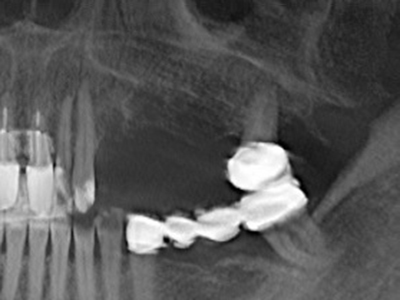

Fig. 15: The one-year follow-up x-ray examination shows stable conditions at the bone level.

Piezo surgery has additional advantages when harvesting bone blocks. In addition to the high precision with osteotomy described above, the use of the thin saw tips specifically minimizes loss of material. Greater loss of material during harvesting can be expected with the thicker instrument tips, particularly when using Lindemann drills (Lakshmiganthan, Gokulanathan et al. 2012). The basal separation, which is necessary particularly for retromolar block transplants, is simplified by specially designed rectangular saws, with the result that piezo surgery is viewed as a precise, simple and safe procedure for harvesting retromolar bone blocks (Happe 2007) (Fig. 1-12).

The splitting procedure is particularly atraumatic and there is no significant loss of dimension when using piezosaws, and there are no significant differences between implants in split jaws and implants in an alveolar ridge without a bone deficit (Chiapasco, Zaniboni et al. 2006, Danza, Guidi et al. 2009). However, sufficient continuous irrigation is essential, particularly with locally restricted and deep splitting to prevent thermal stress in the apical osteotomy regions.